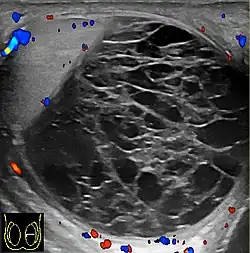

Fig. 3. Seminoma. (a) Seminoma usually presents as a homogeneous hypoechoic nodule confined within the tunica albuginea. (b) Sonography shows a large heterogeneous mass occupying nearly the whole testis but still confined within the tunica albuginea, it is rare for seminoma to invade to peritesticular structures.

Approximately 95% of malignant testicular tumors are germ cell tumors, of which seminoma is the most common. It accounts for 35%–50% of all germ cell tumors. Seminomas occur in a slightly older age group when compared with other nonseminomatous tumor, with a peak incidence in the fourth and fifth decades. They are less aggressive than other testicular tumors and usually confined within the tunica albuginea at presentation. Seminomas are associated with the best prognosis of the germ cell tumors because of their high sensitivity to radiation and chemotherapy.

Seminoma is the most common tumor type in cryptorchid testes. The risk of developing a seminoma is increased in patients with cryptorchidism, even after orchiopexy. There is an increased incidence of malignancy developing in the contralateral testis too, hence sonography is sometimes used to screen for an occult tumor in the remaining testis. On US images, seminomas are generally uniformly hypoechoic, larger tumors may be more heterogeneous [Fig. 3]. Seminomas are usually confined by the tunica albuginea and rarely extend to peritesticular structures. Lymphatic spread to retroperitoneal lymph nodes and hematogenous metastases to lung, brain, or both are evident in about 25% of patients at the time of presentation.